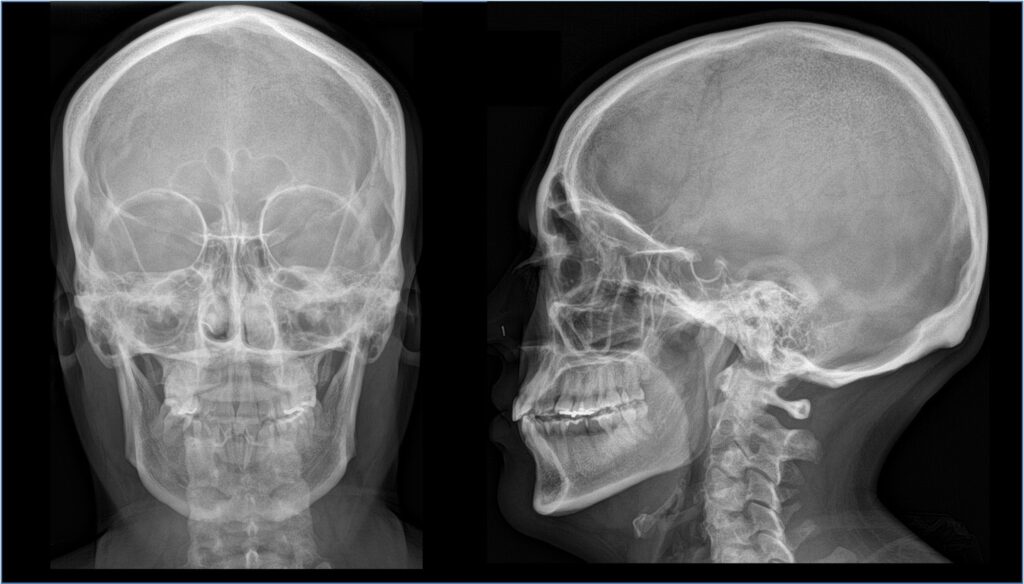

RX cranio e seni paranasali

Cos’è? La RX Cranio e Seni Paranasali è un esame radiologico usato per visualizzare le componenti ossee della scatola cranica e le cavità dei seni